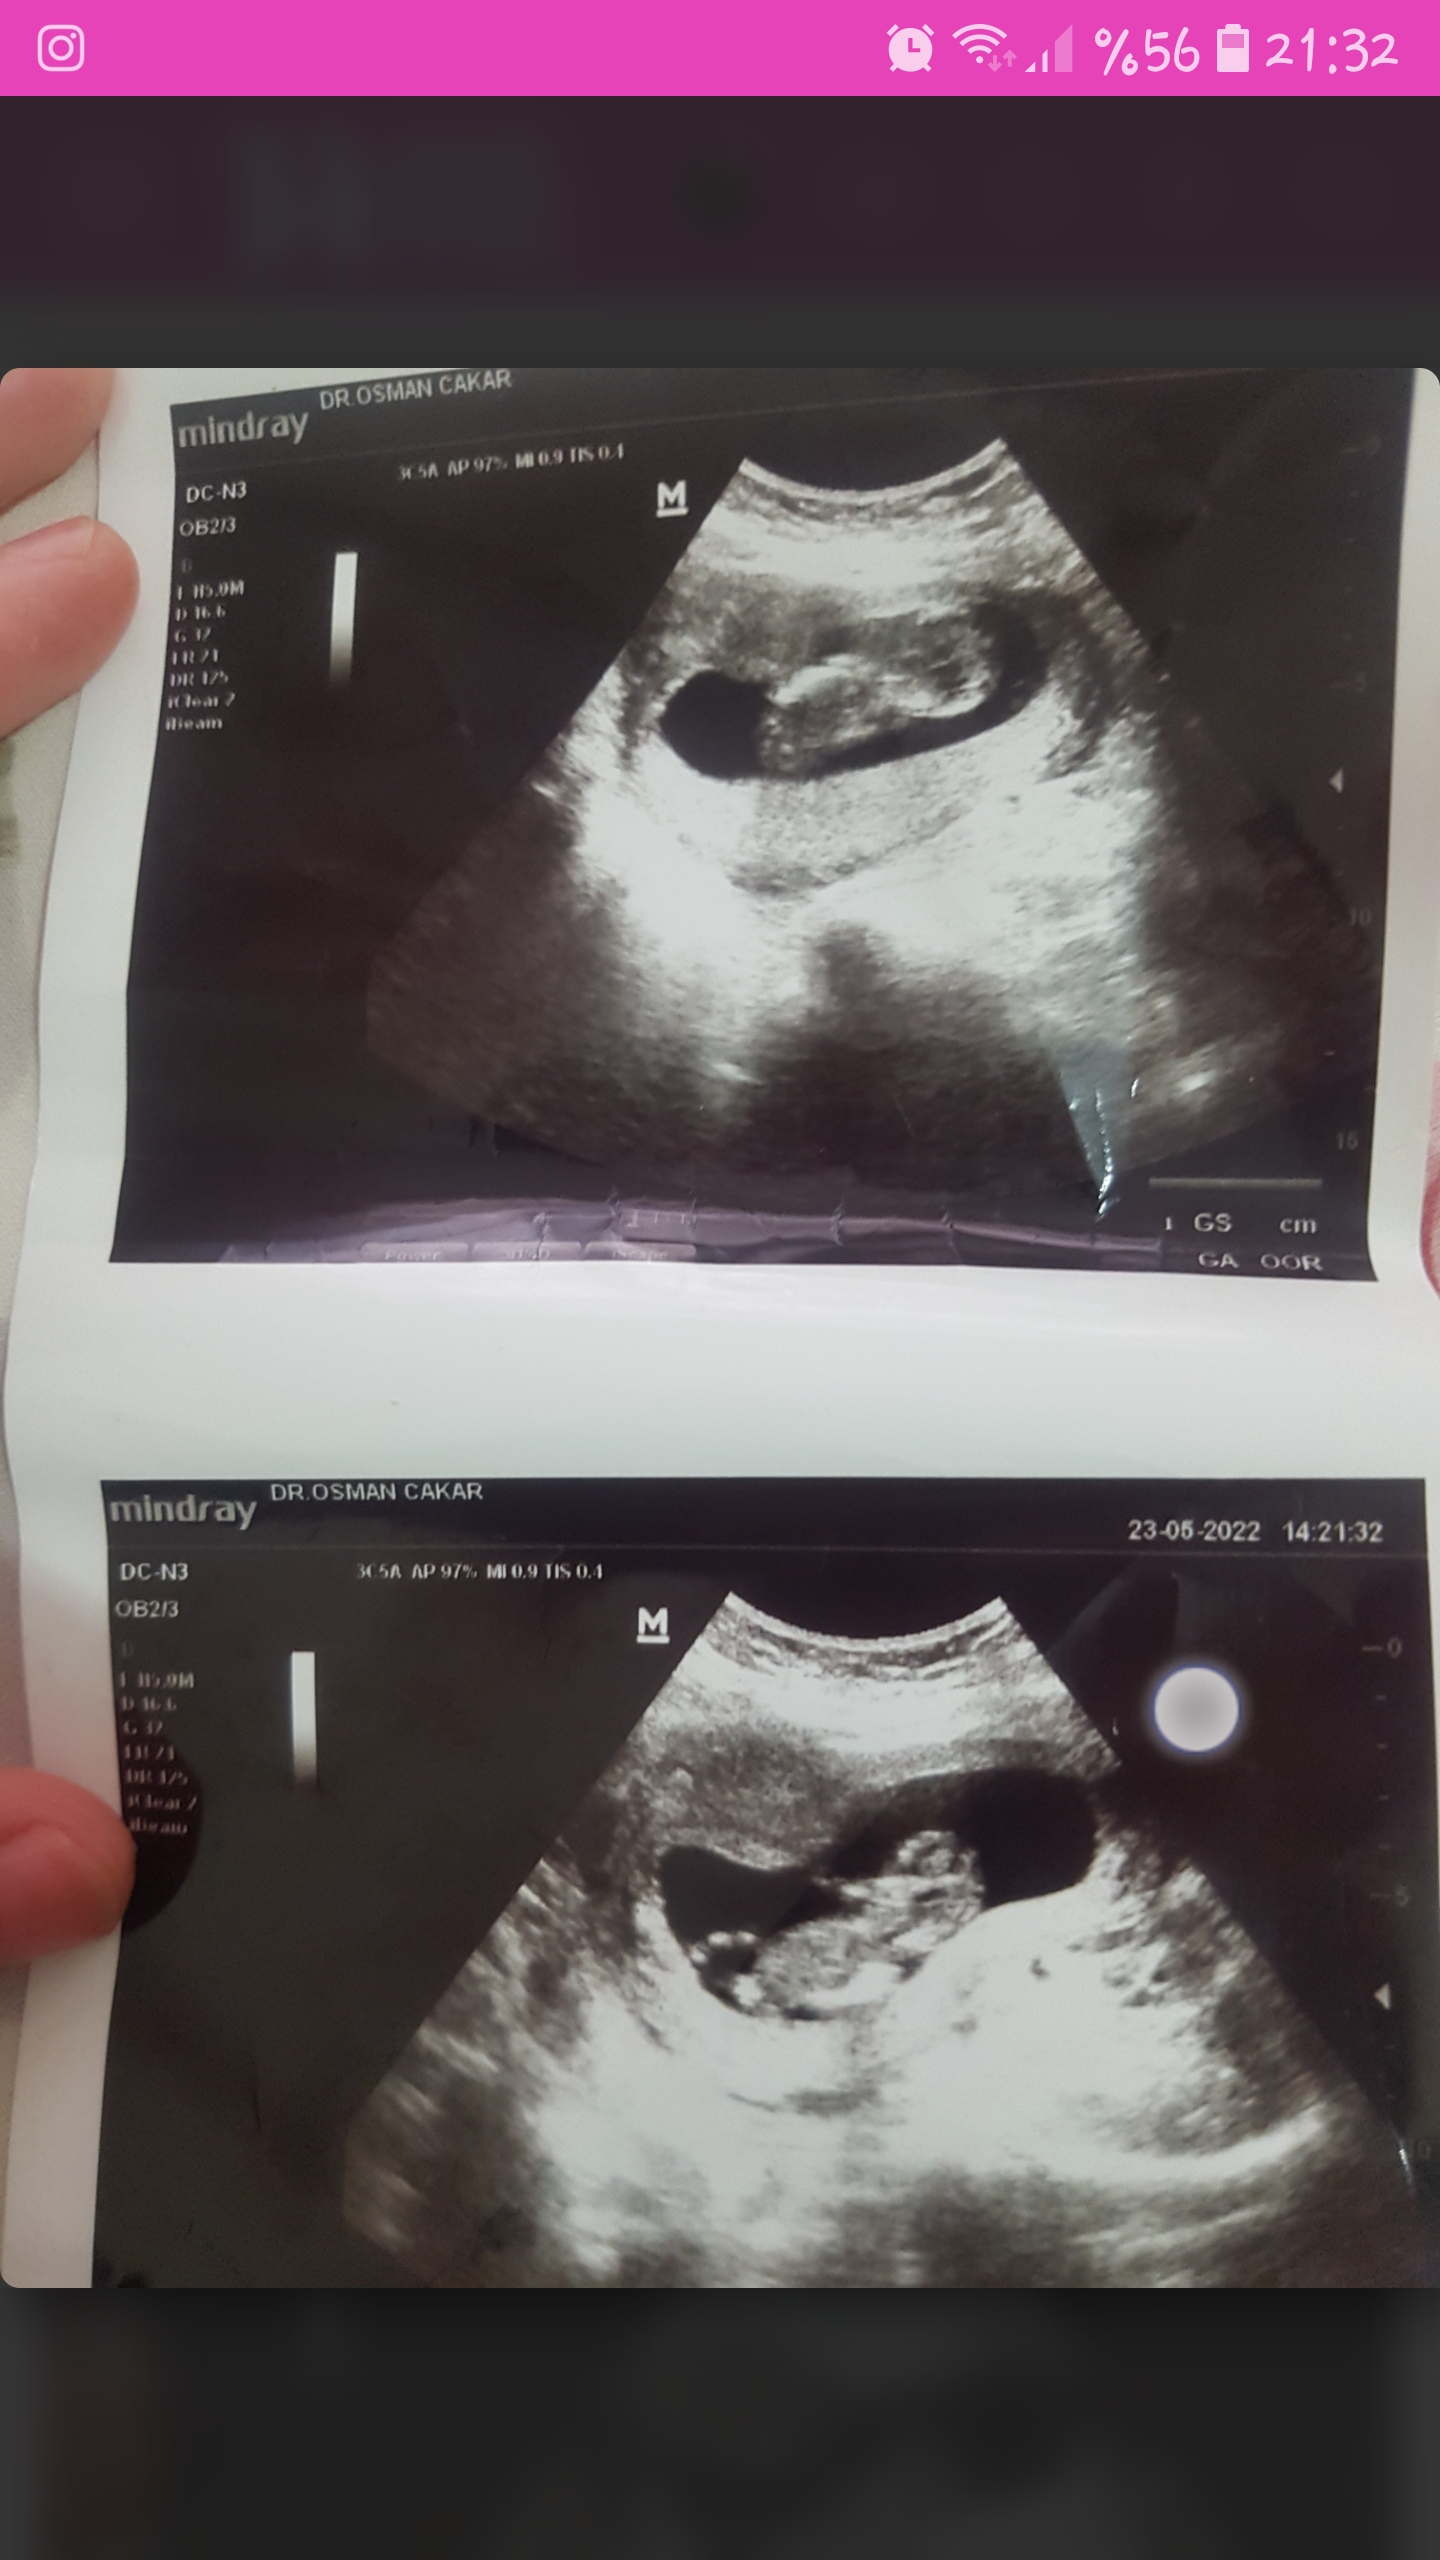

Slm erkek demiştiniz 12 haftalık ultrason fotosu çift yumurta ikizlere hamile olduğumu öğrendim cinsiyet tahmini yaparmisiniz

Ayy 😍😍 gözün aydın balım sanki üst tarafında duran kız gibi hissettim ama alttakine hala erkek diyorum 🤭🤭. Sağlıklı olsunlar da cinsiyet çokta önemli değil 😍🤲🏻